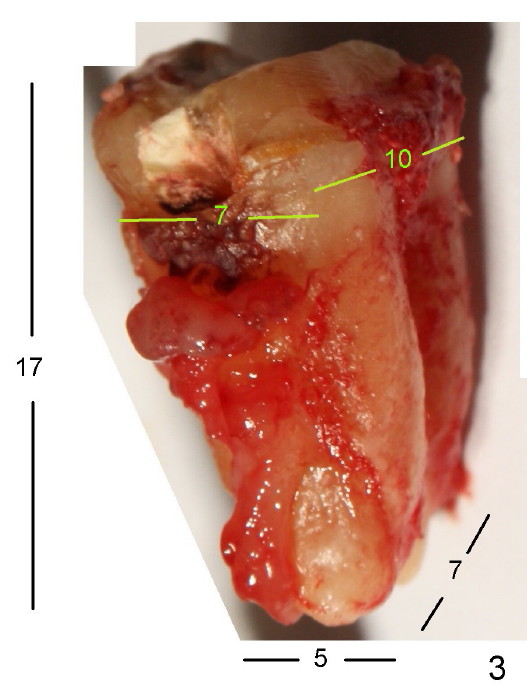

The tooth #31 of a 38-year-old lady has endo perio disease (Fig.1). Due to the large periapical lesion, there will be no solid (new) bone available for primary stability of an immediate implant (Fig.2: 7x17 mm). Yellow dashed line represents the upper border of the Inferior Alveolar Canal (IAC). Infiltration anesthesia is administered first. The mesiodistal widths of the root of the extracted tooth are 10 and 7 mm at the coronal and apical ends, respectively; the buccolingual ones 7 and 5 mm; the length 17 mm (Fig.3). The socket appears much larger than the root (Fig.4). To prevent paresthesia, no drills are used. Instead, a series of tap drills (6,7,8x17 mm) are sequentially inserted into the socket. The largest tap (Fig.5 T; 8x17 mm) binds to the socket securely with separation from IAC. Block anesthesia has to be administered before removal of the tap. A tapered implant (8x17 mm) is placed with insertion torque greater than 60 Ncm (Fig.6 I); allograft mixed with Osteogen is placed around the implant (*). Collagen dressing covers the opening of the remaining socket. The wound is protected with perio dressing, which is partially secured by an abutment (A in Fig.6). No paresthesia is reported by the patient a few hours postop.